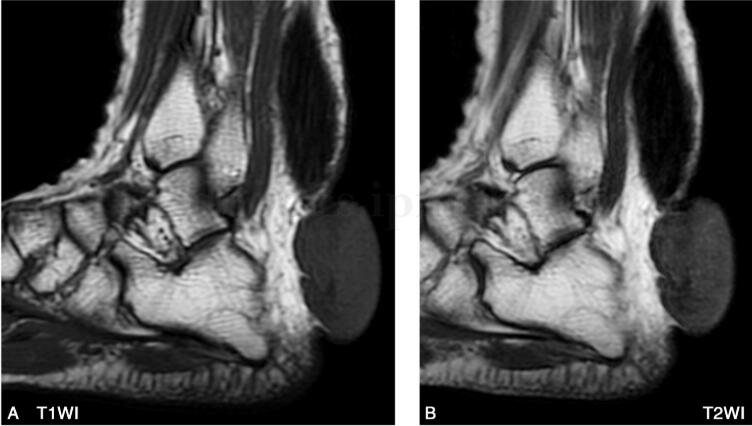

图1 MR:跟腱呈梭形增粗,各序列均以低信号为主,其间夹杂网格状稍高信号。跟腱后下方可见一不规则等低信号结节影,与肌肉信号接近,病灶自右下方包绕跟腱,并向外侧皮下突出

跟腱黄色瘤位于跟腱部位皮下,位置表浅,跟腱普遍增粗,呈梭形,有较为特征性的MR表现,但瘤体本身与跟腱多不能区分,一般情况下病变的信号变化多早于肌腱形态的改变,典型病变在T1WI像上呈跟腱长轴的类似肌肉的较低信号,在T2WI像上也呈较低信号影,其内有斑点状较高信号,在脂肪抑制上则表现的更加显著,病理上低信号为胶原纤维,高信号区域为含脂质的泡沫细胞及炎性反应。

本例于跟腱后下部跟骨附着点后方可见结节状软组织肿块,不完全性包绕肌腱生长,各序列近似于肌肉信号,术中及病理均证实该肿块与肌腱内病变组织成分相同,大体上均呈淡黄色,质软,由纤维组织及泡沫细胞构成,并可见胆固醇结晶。考虑系由于含胆固醇酯的巨噬细胞除在跟腱内灶状聚集外,同时在跟腱周围大量汇聚所致。